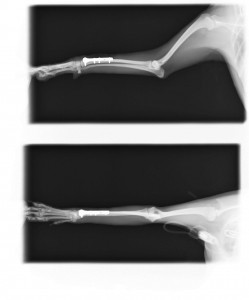

手術後のレントゲン写真

手術後2日ほどで歩行可能になり、術後1ヶ月くらいで昔と変わらずに元気いっぱいで散歩に出かけています。よかったですね(^0^)!